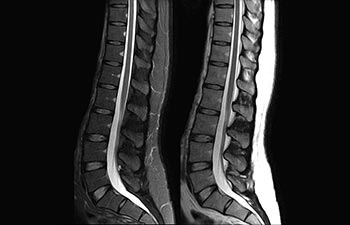

Columna.

Columna lumbar con mDIXON XD